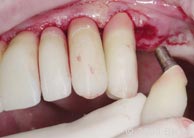

13. |

作减张切口,以便于一体化基台冠的就位。 |